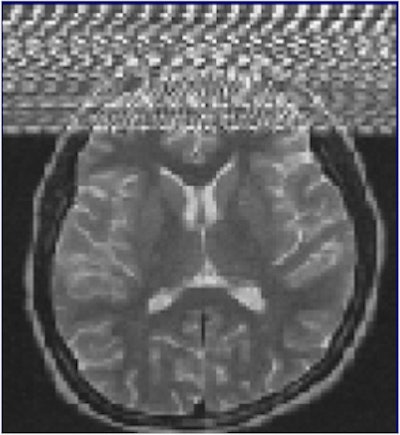

Zipper artifacts, when a radiofrequency (RF) wave interferes with the MRI unit, may occur if a medical device that is not RF-shielded is placed inside the magnet room. Other causes are blinking light bulbs, the examination room door not being tightly closed, and drilling work nearby. Image courtesy of IGK Kusumasuganda, mriforyou.blogspot.co.uk.Motion artifacts occur in the phase-encoding axis of the k-space encoding, which usually happens in the vertical axis of the MR image, and this encoding direction of the k-space is considered "slow" and can even take some minutes, they stated in an e-poster at ECR 2015. As the image is being encoded or acquired, motion can occur and different timings are recorded, and hence the final image will not have clear borders and "ghost images" or even spatial blurring occur in the phase-encoding axis of the image.

Zipper artifacts are related to the contamination of electromagnetic energy in the MRI suite. MRI suites should be isolated in order to avoid external interference from other sources of RF or from electronic equipment like radios and cellphones that emit electromagnetic signal and can cause interference. Contamination usually happens because of equipment that is wrongly brought into the MRI suite, and the artifact disappears as soon as this external source of frequency is removed from the MRI suite. If the artifact persists, it probably means the isolation of the MRI suite has been compromised.